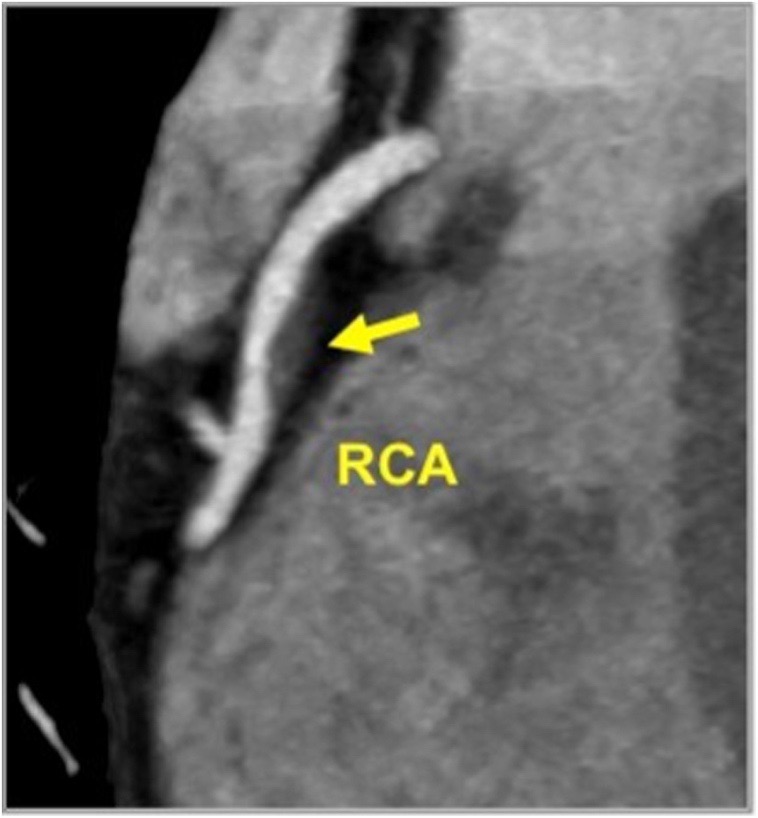

Gambar 3. Gambar penumpukan plak kalsium pada pembuluh darah koroner yan terlihat pada CT Scan